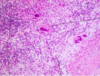

Micro:

Tuberculous pericarditis

• Typical granuloma consists of:

- necrotic center (caseation)

- zone of epitheloid cells (modified histiocytes)

- Langhans’ giant cells

- outer margin of lyphocytes.

granulomas in pericardium:

- epithelioid cells

- caseous necrosis

- langhan cells

- lymphocytes

consists of:

- necrotic center (caseous necrosis)

- zone of epithelioid cells (modified histocytes)

- langhans giant cells

- granulation tissue

- outer margin of lymphocytes

- surface of epicardium is covered by fibrinous exudate* and *inflammatory infiltrate